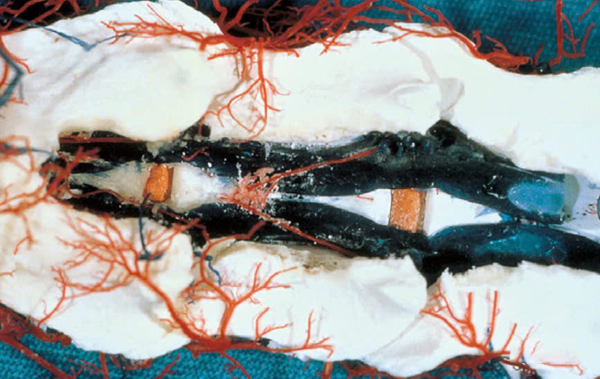

Ý nghĩa lâm sàng của xoang tĩnh mạch xương sống trong phẫu thuật cột sống cổ:

- Hình ảnh chế phẩm latex giúp làm rõ vị trí của xoang tĩnh mạch xương sống ở đáy ống cột sống. Khi loại bỏ mảng xương sống phía trên, ta có thể thấy đĩa đệm (màu cam) và sự tụ tập của các xoang tĩnh mạch ở giữa thân đốt sống, tách ra phía trên đĩa đệm.

- Điều này nhắc nhở chúng ta rằng khi thực hiện phẫu thuật từ phía bụng, cần đặc biệt hạn chế chiều rộng khoang phẫu thuật để tránh tổn thương các xoang tĩnh mạch. Nếu tổn thương, nguy cơ chảy máu nhiều là rất cao.

- Khuyến nghị phẫu thuật:

- Chiều rộng khoang mổ không vượt quá 50% chiều rộng thân đốt sống để bảo toàn tính ổn định.

- Chiều dài khe mở không nên vượt quá điểm giữa của thân đốt sống, vì ở giữa là vị trí gần nhất của hai xoang tĩnh mạch cạnh thân đốt sống.